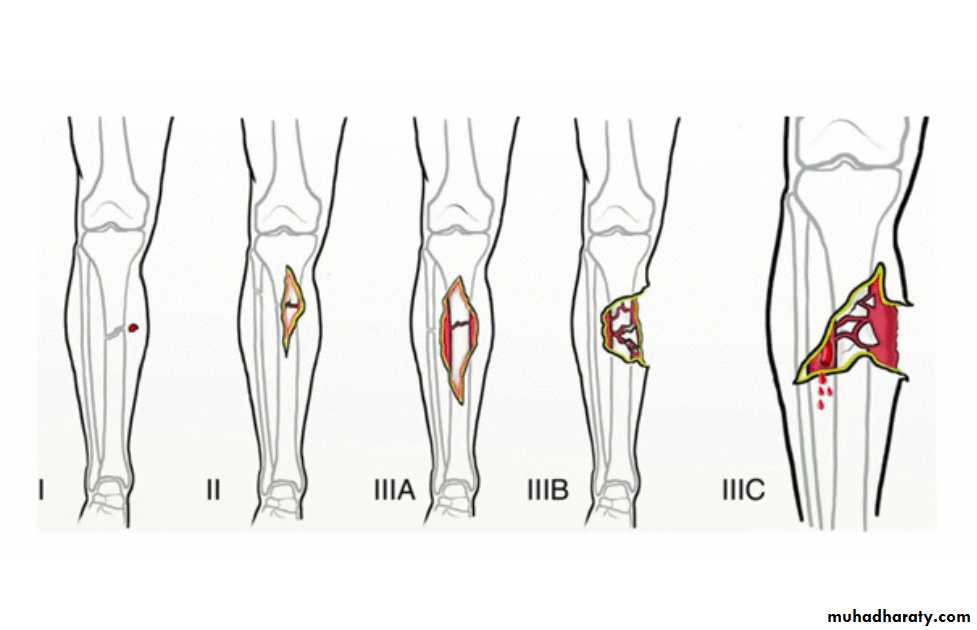

Open Fractures

A break in skin and underlying soft tissues leading directly to communicating with the fracture

Classification of open fractures

Emergency Management of Open Fracture

fracture stabilization ( according to grade)